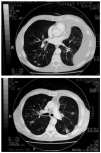

Fig. 2. Tomografía axial computarizada torácica en la que se observan el derrame pleural izquierdo y las imágenes nodulares múltiples bilaterales.